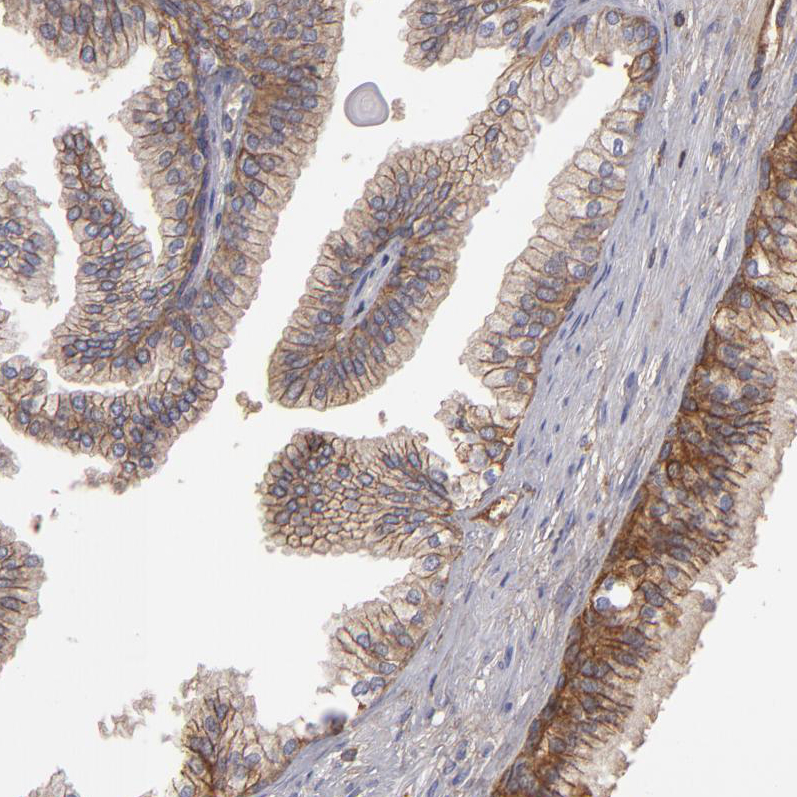

Immunohistochemistry analysis in human prostate and liver tissues using HPA002476 antibody. Corresponding ABCC4 RNA-seq data are presented for the same tissues.